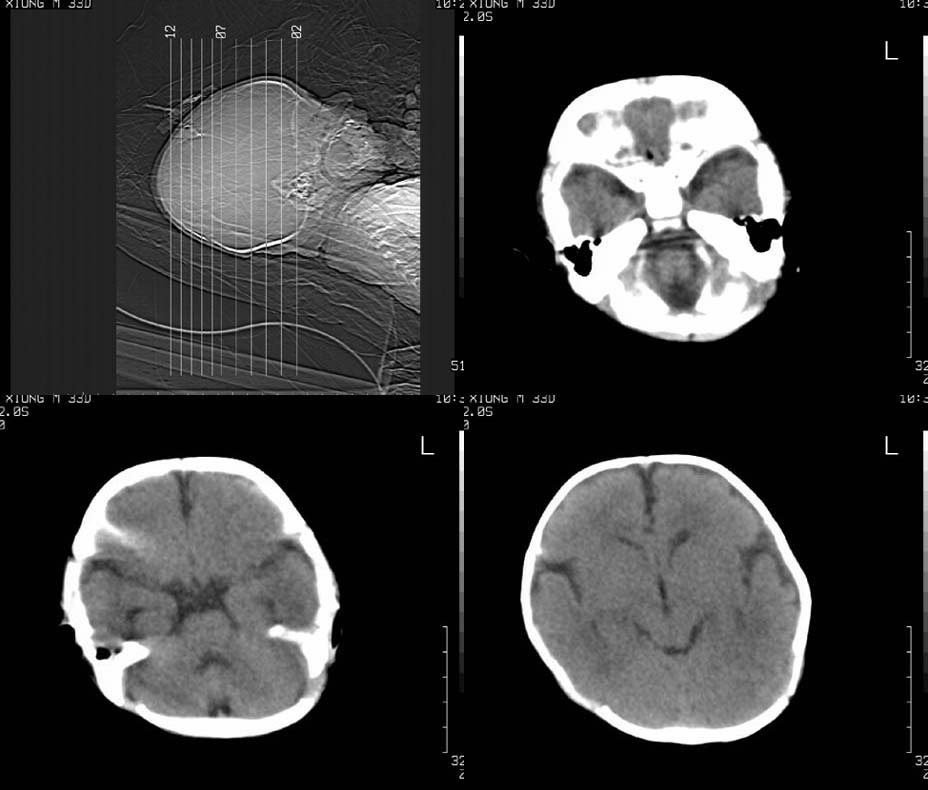

患儿,男,30天。出生时即发现两侧头顶部肿块,触诊似乒乓球样,其余各项检查未见异常。ct扫描:两侧顶骨外侧软组织密度影,ct值约29hu,脑皮质ct值约28.1hu。外缘尚见骨样结构。

双侧顶部软组织明显肿胀,相应部位骨质可见多处缺损 考虑 双侧顶骨嗜酸性肉芽肿可能性大。